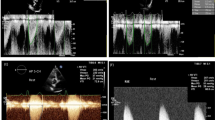

Myocardial fibrosis in AS patients can be described by the reduction of mitral annular plane systolic excursion (MAPSE) even in the presence of normal LV ejection fraction (LVEF) [39,40,41,42]. MAPSE is measured by M-Mode through the septal mitral annulus in the apical 4-chamber view and serves as a surrogate parameter for myocardial fibrosis. MAPSE < 5 mm indicates AS patients with severe fibrosis. In patients with low-gradient AS MAPSE < 9 mm is able to distinguish between moderate and severe AS [42].

The position of the sample volume in the LVOT has to be accurately adjusted at the same position and time point of the cardiac cycle where DLVOT and CSALVOT are measured. Minimal variations of the position of the sample volume cause significant alterations of the VTILVOT. Depending on the LVOT size and the intercept angle between the ultrasound beam and the direction of LVOT blood flow it is important to position the sample volume near the septal wall to optimize Doppler angulation (Fig. 6). In general, the apical long axis view enables a better control for checking the correct position of the sample volume at the region of DLVOT measurement (in contrast to the five-chamber view, in which a visual control is not possible). Furthermore, acquisition of the Doppler spectra using the duplex or triplex mode enables to check, whether the sample volume position is at the correct position at mid systole or not.

Illustration of the effect of PWD sample volume position on LVOT spectrum in a normal AV. The yellow circle represents the correct position. The red circle is too far away from the aortic annulus. The blue circle is too near to the anterior mitral leaflet. The green circle is at the aortic annulus between the cusps. In normal AV PWD spectra of LVOT and AV are normally equal, because diameters are equal